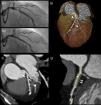

A 68-year-old man with a history of coronary artery disease was admitted with non-ST-elevation myocardial infarction. Coronary angiography revealed 95% stenosis of the proximal left anterior descending artery (Figure 1A1). The patient underwent percutaneous coronary intervention with implantation of a 3.5 mm×18 mm bioabsorbable everolimus-eluting poly(lactic acid) scaffold (Abbott Vascular, Santa Clara, CA) (Figure 1A2). As part of a prospective study, 64-slice CT angiography (SOMATOM Sensation 64 scanner, Siemens, Forchheim, Germany) was performed at the first month follow-up. Radiopaque indicators (arrows) at the edges of the scaffold were the only discernible traces on volume-rendered imaging (Figure 1B) and in maximum intensity projection reconstructions (Figure 1C).

Coronary angiography, showing significant left anterior descending stenosis (A1) and angiographic outcome after placement of a bioabsorbable scaffold (A2). Multislice computed tomography angiography: volume rendering (B) and maximum intensity projection reconstructions (C), revealing the radiopaque indicators (arrows) at the edges of the scaffold. Virtual histology technique showing the non-calcified atherosclerotic plaque (arrows) excluded by the stent (D).

Virtual histology (Aquarius workstation, TeraRecon Inc., San Mateo, CA) showed the non-calcified atherosclerotic plaque (arrows) excluded by the stent (Figure 1D). Cross-sectional in-stent lumen areas were measured, with a minimal lumen area of 5.54 mm2. No significant lumen loss was detected.